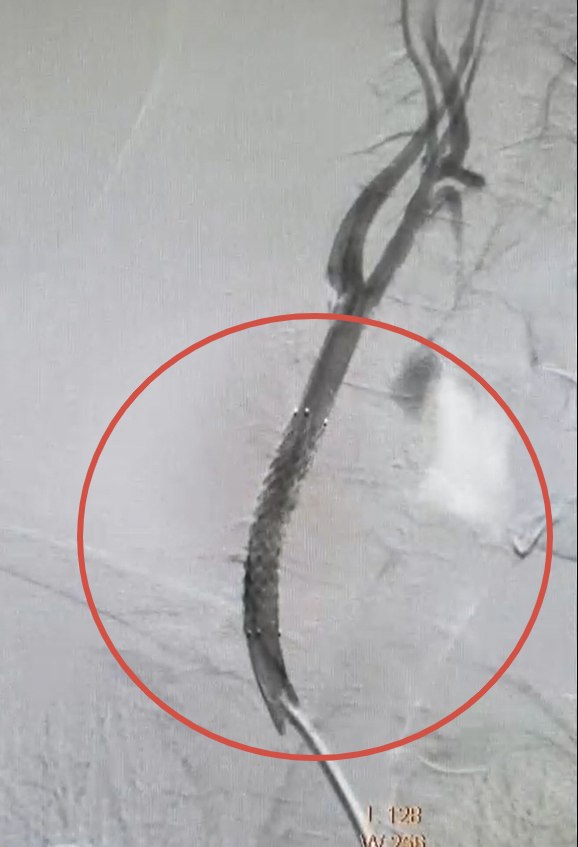

32-летний курянин получил тяжелое ранение яремной вены и сонной артерии в результате удара беспилотника. Позже у него развились осложнения — аневризма сонной артерии — растяжение участка сосуда с истончением стенки.

Сосудистые хирурги Валерий Казанов и Алексей Подтуркин выполнили небольшой надрез в бедренной артерии пациента, после чего направили инструменты к пораженному участку шеи. В артерию установили стент-графт — трубку с металлической опорой, которая укрепила стенку сосуда.

Продолжительность операции составила около часа.